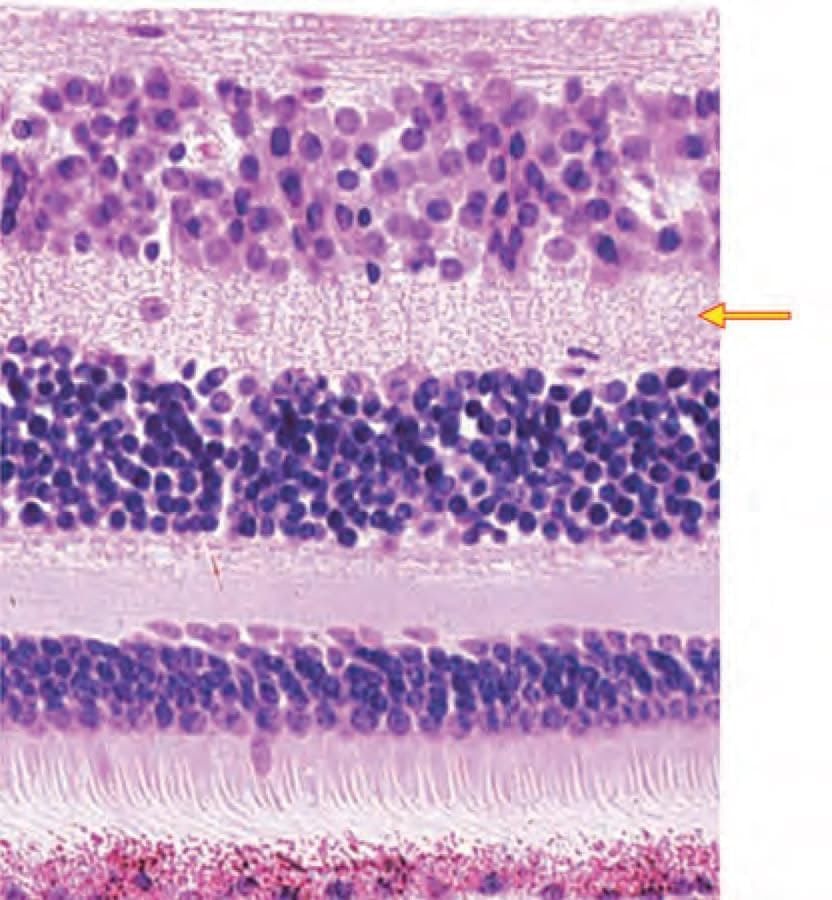

Identify the marked layer in the given histological section: (AIIMS Nov 2019)